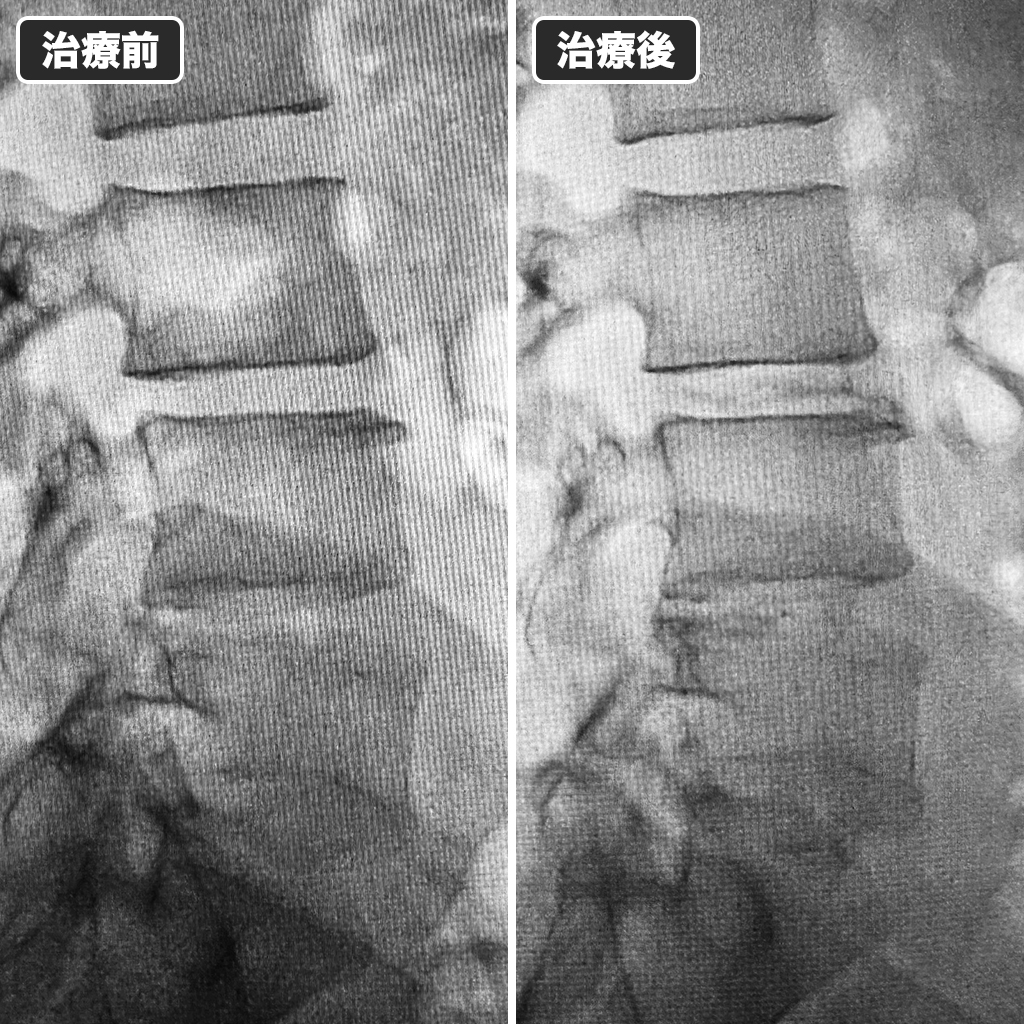

治療前後のレントゲン写真

3箇所の椎間板に損傷部位が確認できたので、全てにディスクシール治療を行いました。左側が治療前、右側が治療後になります。